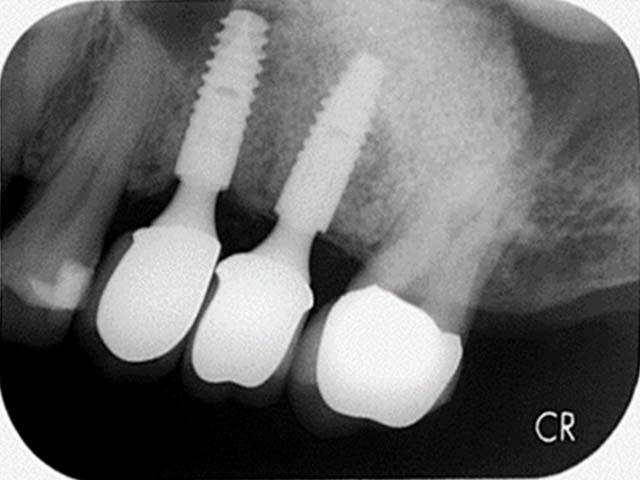

鼻竇增高術(側窗) 首頁 案例分享 人工植牙 鼻竇增高術(側窗) 鼻竇增高術(側窗) 製作多年的牙橋,牙根斷裂,發炎 鼻竇增高術 側面開窗 抬高鼻竇 鼻竇增高術 置入骨粉 覆蓋再生膜,保護骨粉 術後追蹤,傷口良好 裝戴正式假牙 完成 8年追蹤 左上牙根斷裂 植牙重建 九年追蹤